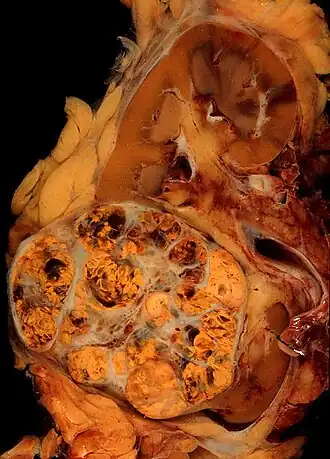

Macroscopisch onderzoek (onderzoek met het blote oog) toont een gelige, multilobulaire (meerlobbige) tumor in de nierschors met vaak zones met necrose (afgestorven weefsel), bloeding en verlittekening.

Bij licht-microscopisch onderzoek is te zien dat de tumorcellen samenklonteren tot strengen, papillen, buisstructuren of nestjes. De individuele cellen zijn atypisch (afwijkend van de normale structuur van de niercel), polygonaal (veelhoekig) en groot. Omdat de cellen glycogeen en lipiden opslaan in het cytoplasma zien ze er helder (Engels: clear), vetbeladen uit; de celkern blijft centraal in de cel, de celmembraan is duidelijk zichtbaar. Sommige cellen zien er kleiner uit met eosinofiel cytoplasma en lijken op normale tubuluscellen. Het stroma, het omringende bindweefsel van het gezwel, is verminderd, maar wel gevacuoliseerd (met vacuolen). De tumor drukt op het omringende parenchym van de nier en vormt een pseudokapsel.[24]